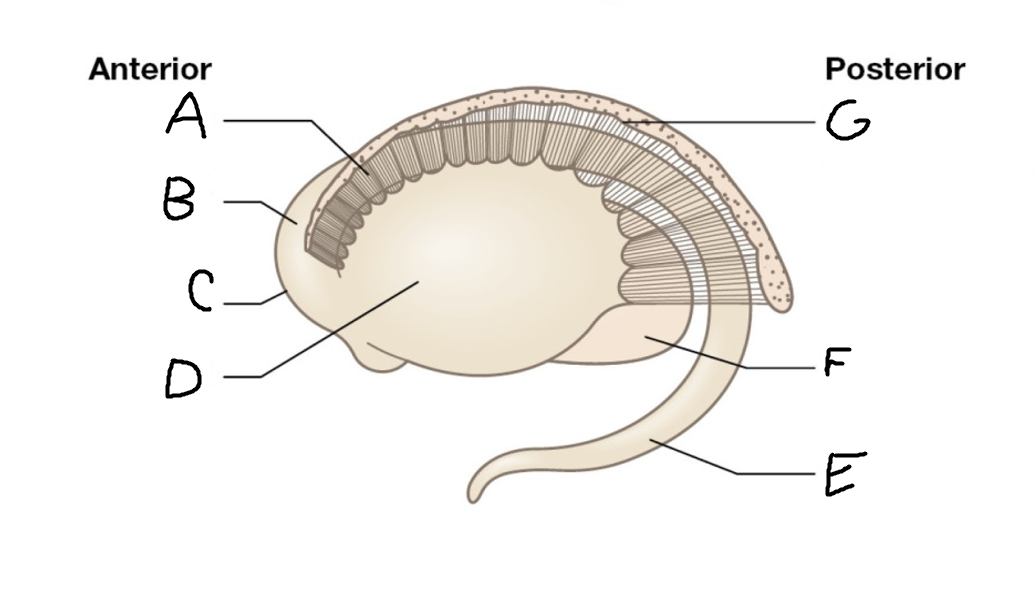

A

head of caudate nucleus

C

putamen

D

external segment of globus pallidus

E

internal segment of globus pallidus

F

third ventricle

G

thalamus